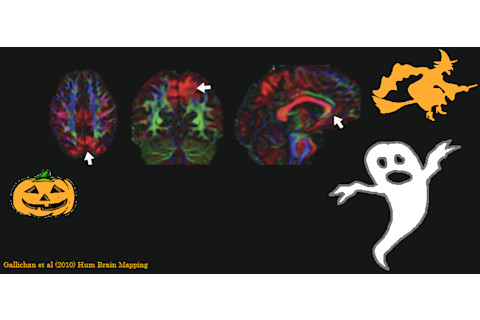

This tale is loosely based on the true story of the 'DTI vibration artefact

'. An artefact (pictured) was discovered to be affecting certain implementations of the Diffusion Tensor Imaging sequence. Lots of researchers had been using it, unwittingly collecting data, before someone revealed the problem. That story ended relatively happily, because someone worked out how to clean up the data post hoc

, but this still left the awkward question of how to interpret results that had already been published based on the affected data

Gallichan D, Scholz J, Bartsch A, Behrens TE, Robson MD, & Miller KL (2010). Addressing a systematic vibration artifact in diffusion-weighted MRI. Human Brain Mapping, 31 (2), 193-202 PMID: 19603408